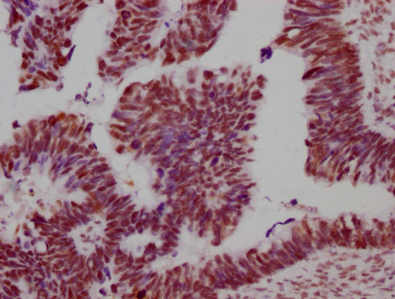

圖:SMC?A單克隆抗體[8C11]稀釋比例為1:100,用于染色石蠟包埋的人卵巢癌組織,實(shí)驗(yàn)在Leica Bond系統(tǒng)上完成。經(jīng)過脫蠟和水化后,使用檸檬酸緩沖液(pH 6.0)通過高壓進(jìn)行抗原修復(fù)。切片用10%正常山羊血清封閉30分鐘。然后將一抗(含1% BSA)在4℃孵育過夜。一抗通過抗兔IgG聚合物(標(biāo)記有HRP)檢測,并使用0.5% DAB進(jìn)行顯色。